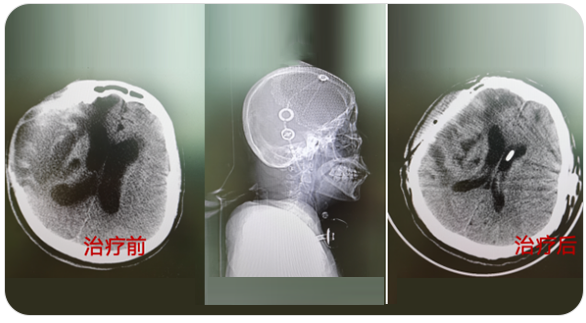

精通颅内动脉瘤介入栓塞和手术夹闭双技术,系统掌握脑动静脉畸形、颈内动脉海绵窦漏、硬脑膜动静脉漏等颅内血管疾病的诊疗和手术,精通颈动脉、椎动脉狭窄的血管内重建技术,以及颈动脉狭窄的内膜剥脱手术技术。在颅内肿瘤、椎管内肿瘤、颅脑损伤、高血压脑出血等疾病的诊治和手术,脑功能性疾病立体定向手术治疗等方面也积累了丰富的经验。